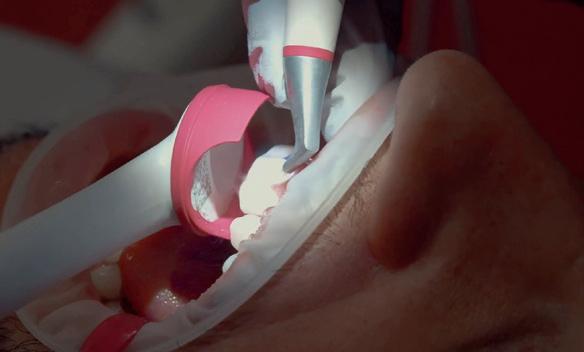

RECONSTITUIREA țesuturilor moi periimplantare. Scopul acestui raport de caz este de a demonstra procedurile chirurgicale utilizate pentru corectarea unui defect al țesuturilor moi periimplantare folosind țesutul moale interdentar în combinație cu tuberozitatea ca locație donatoare de țesut conjunctiv, utilizând o abordare prin tunelizare într-o zonă estetică.